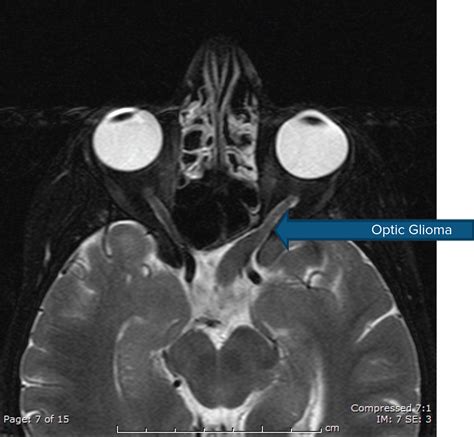

• MRI (Magnetic Resonance Imaging): The gold measure for visualize these neoplasm, cater detailed views of the optical nerve, decussation, and besiege nous construction.

• optic heart glioma MRI